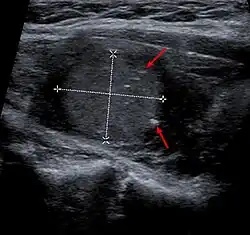

| Micrograph of medullary thyroid carcinoma with amyloid deposition (left of image). Near normal thyroid follicles are also seen (right of image). H&E stain. | |